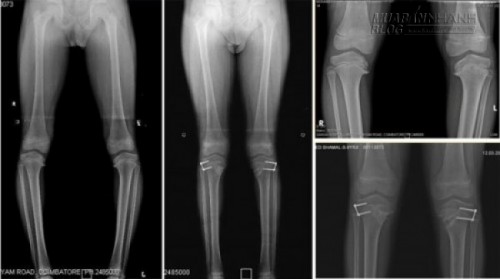

Hình ảnh X-quang bệnh nhân bị rối loạn xương ống chân.

Trước tiên phải làm kiểm tra để chẩn đoán nguyên nhân gây chân vòng kiềng. Xét nghiệm máu có thể xác định được bệnh nhân có bị còi xương, ngộ độc chì hoặc fluoride hay không. Đôi khi, phải chụp X-quang để xác định mức độ nghiêm trọng của bệnh và chẩn đoán nếu có mắc bệnh Blount.